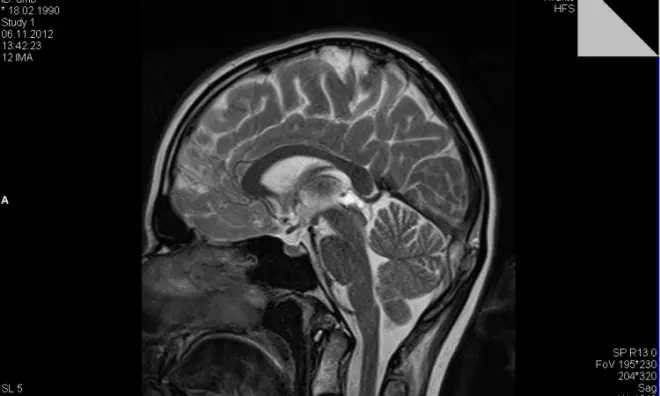

Доброякісна кіста порожнини прозорої перегородки головного мозку є досить поширеним недугою, який сьогодні можна виявити за допомогою МРТ або томографії. Серед пацієнтів з доброякісними захворюваннями головного мозку, пухлина прозорою перегородки діагностують більш ніж у 20% людей.

Визначити наявність і розміри пухлини в корі головного мозку допомагає магнітно-резонансна або комп'ютерна томографія. Такі процедури зазвичай є страхітливими для людини, проте вони не тільки нешкідливі, але і мають вирішальне значення в діагностиці кіст головного мозку . Томографія дозволяє швидко і точно виявити місце прикріплення кісти прозорого відділу головного мозку, її розміри, патогенність і масштаби впливу. Також за результатами дослідження стає ясно, чи небезпечна кіста і наскільки сильною може бути її вплив на організм.

Якщо пухлина збільшилась досить сильно і почала свій вплив на здорові ділянки головного мозку, її потрібно терміново лікувати. Спочатку процес лікування починається з діагностики МРТ головного мозку кісти прозорої перегородки і вивчення першопричин формування освіти.

Крім визначення точного місця розташування кісти прозорої перегородки МРТ дозволяє уточнити розміри пухлини, характер її впливу на сусідні тканини і приблизну швидкість росту. Додатково в рамках діагностики проводиться комплексне обстеження організму. У пацієнта беруться аналізи, вимірюється артеріальний тиск, проводяться дослідження на генетичні відхилення або хронічні захворювання, здатні надавати прямий або опосередкований вплив на швидкість росту і патогенність кісти.